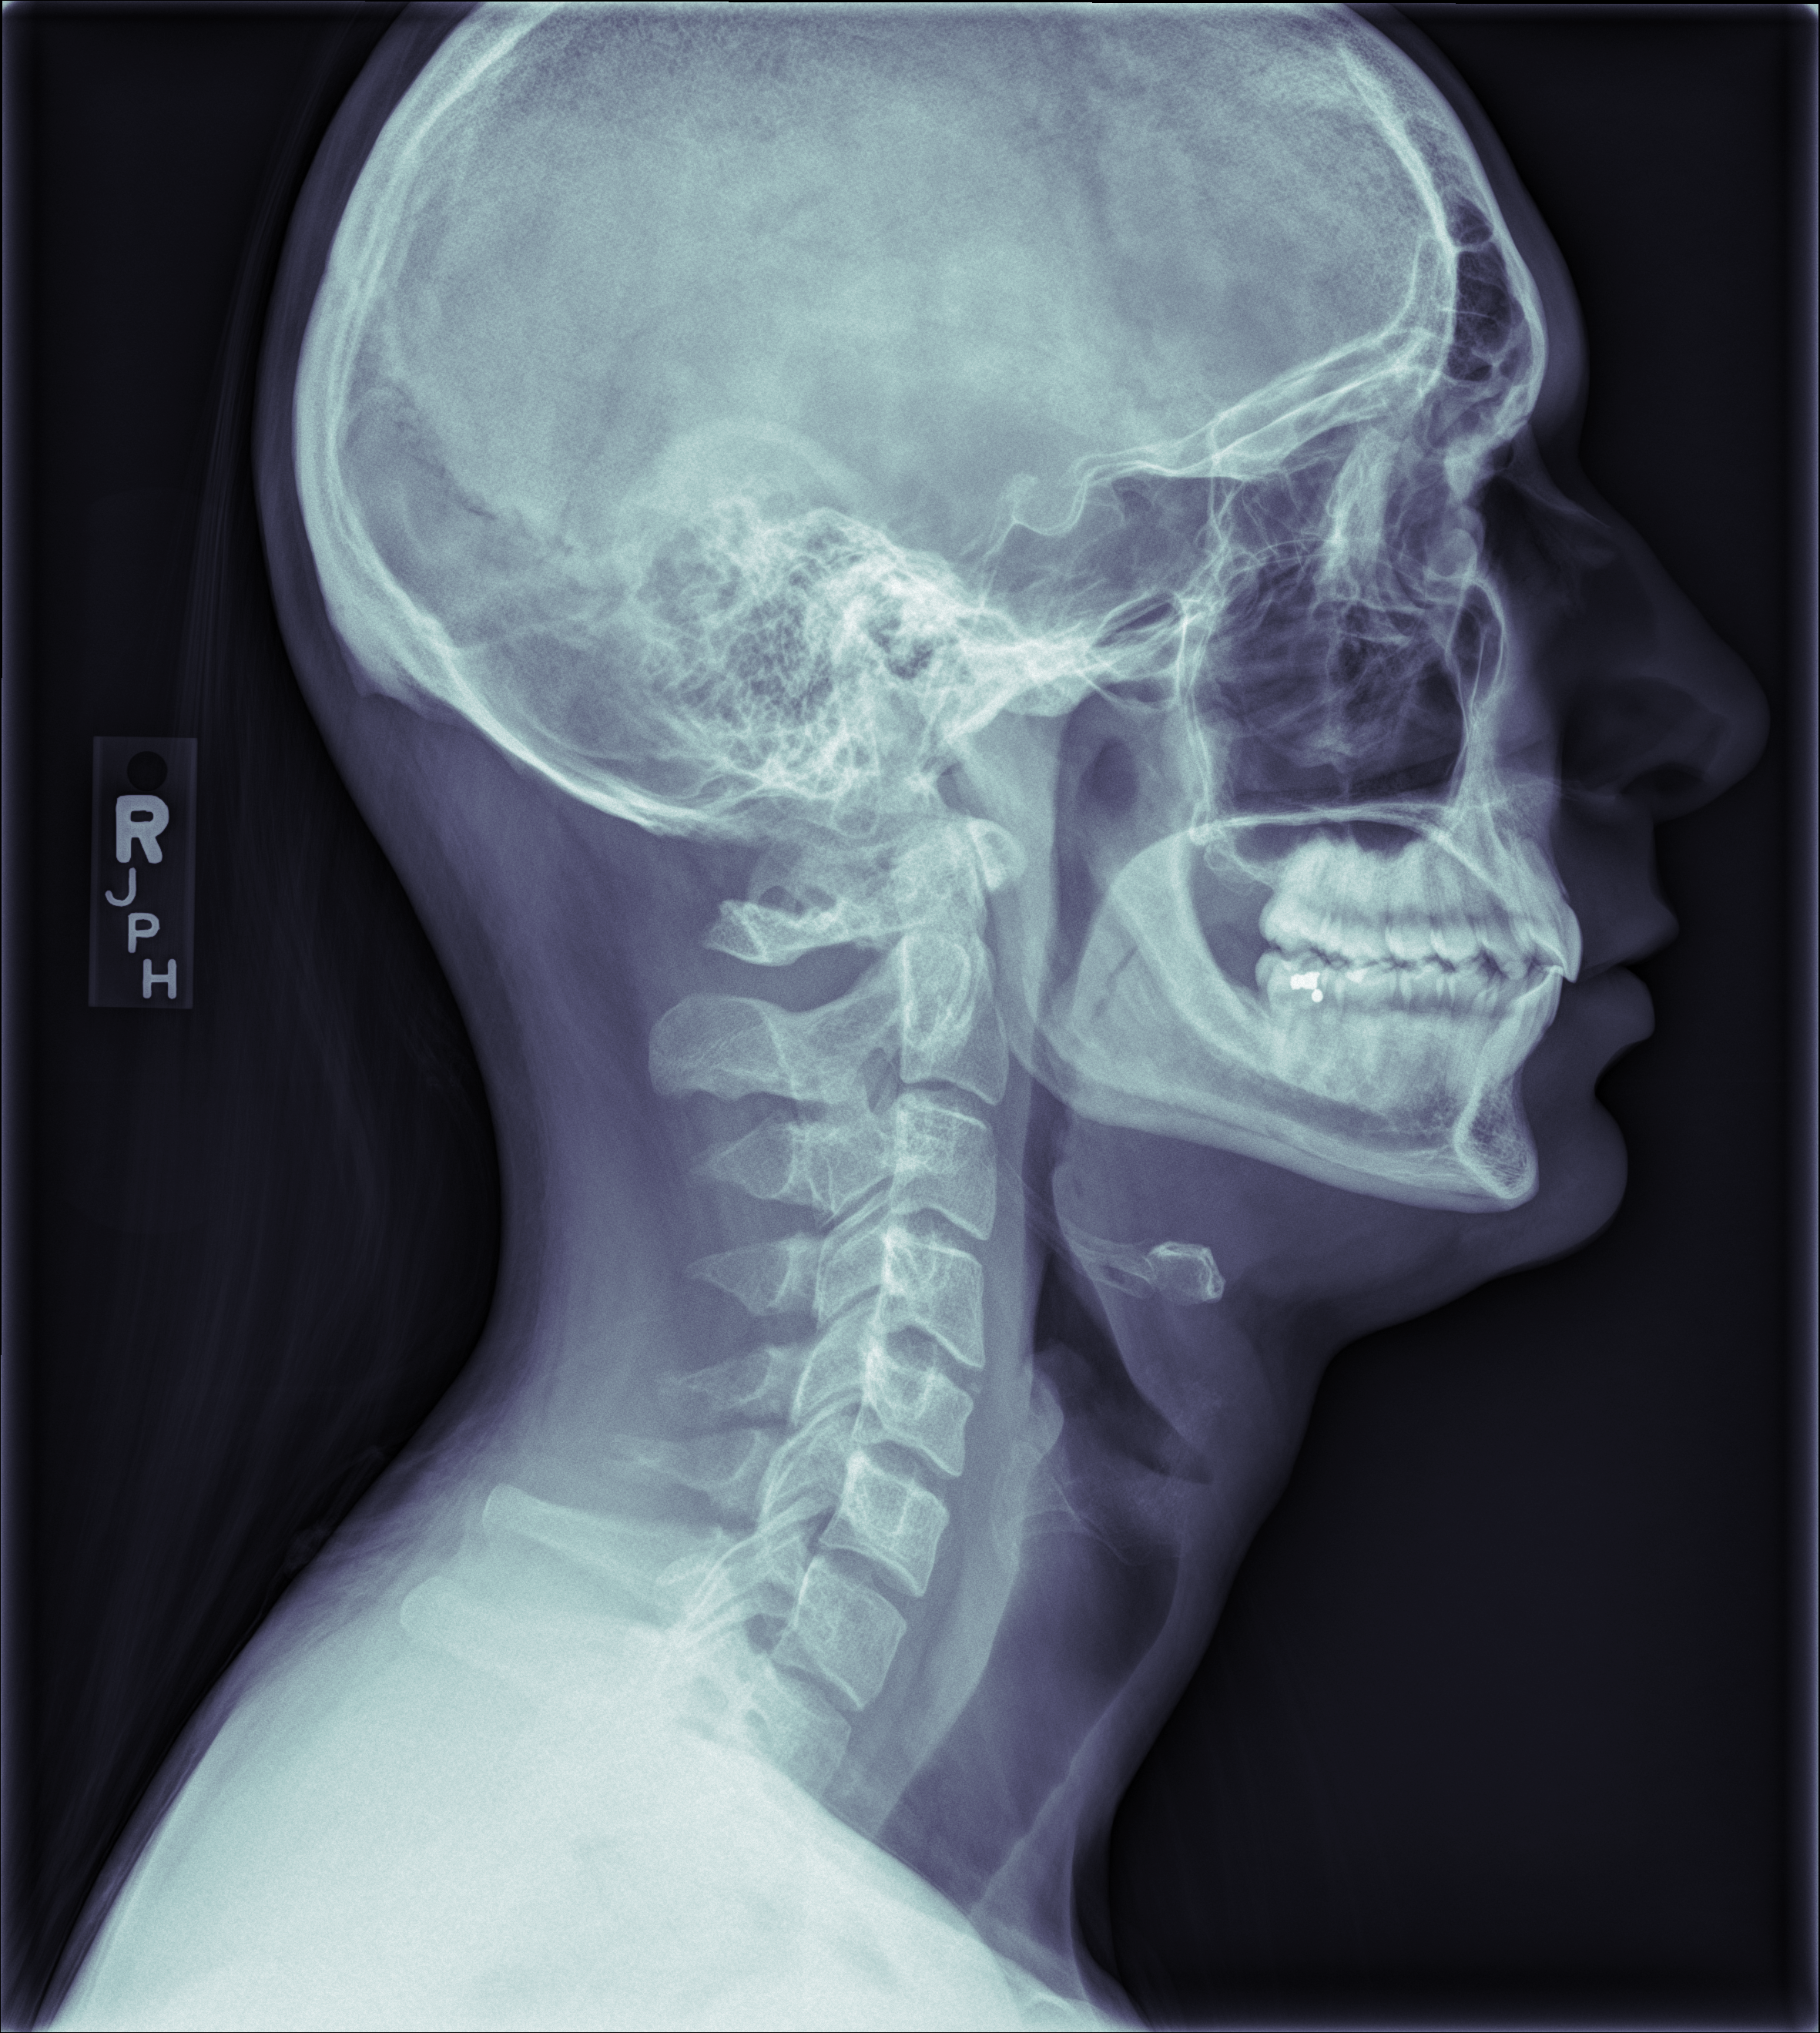

The xray tech told me to slouch for this one: "the complete opposite of what your mother always told you"

You can see my hyoid really clearly, as well as the filling in my right, lower, rearmost molar, and the bony bridge of my nose, and a bit of my hair, and my spinal cord, and those huge fins on the back of the neck vertebrae. You can see how my upper rear molars are tipped and hadn’t dropped all the way. I’ve since gotten braces and worn rubber bands to readjust them. At the time I wasn’t even aware that was abnormal.